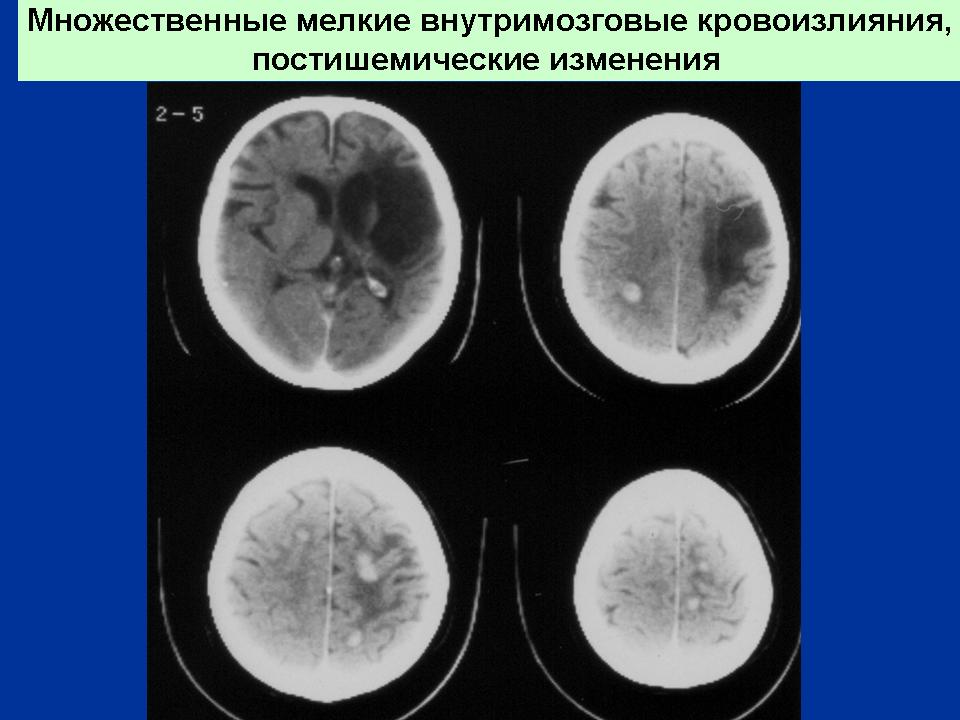

ГМ. Гематомы. Инсульт. Геморрагический и ишемический. +

Геморрагический инсульт